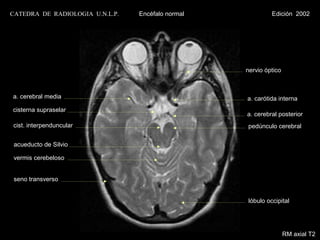

CATEDRA DE RADIOLOGIA U.N.L.P.   Encéfalo normal              Edición 2002

nervio óptico

a. cerebral media

tallo hipofisario

cist.supraselar

cist. interpenduncular                              cist. crural

cist. ambiens

acueducto de Silvio

cist. cuadrigeminal

vermis cerebeloso

lóbulo occipital

RM axial T1 con contraste